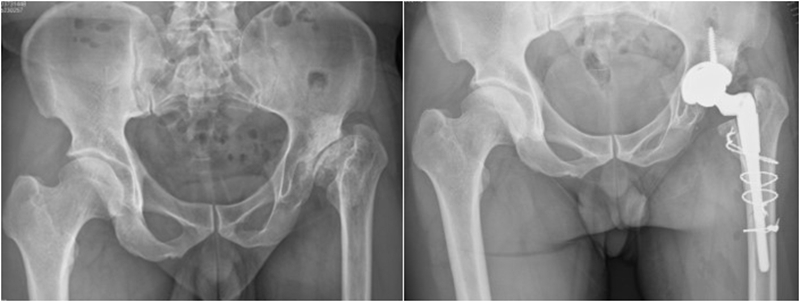

Ⅱ、股骨颈畸形---髋内外翻,offset异常

(1)颈干角偏小(<120°)——髋内翻

髋内翻,颈干角小,偏心距较大,选择high-Offset假体,以维持外展肌张力。

(2)颈干角过大(>140°) ——髋外翻

髋外翻多见于DDH,难度在于股骨距内侧皮质阻挡假体完全坐入髓腔,强行打击造成股骨距骨折。

Ⅲ、干骺端畸形

硬化骨、骨赘、骨质疏松、髓腔宽大

转子间骨折畸形愈合后常导致干骺端畸形,干骺端遗留大量硬化骨或髓腔成角,术中需在确认髓腔开口位置后,首选用小骨刀或高速磨钻去除硬化骨,打通髓腔。

干骺端畸形还可引起髓腔增宽,骨量减少,骨质疏松,不能为近端压配固定型的假体提供良好稳定。宜选用全微孔涂层远端固定假体。